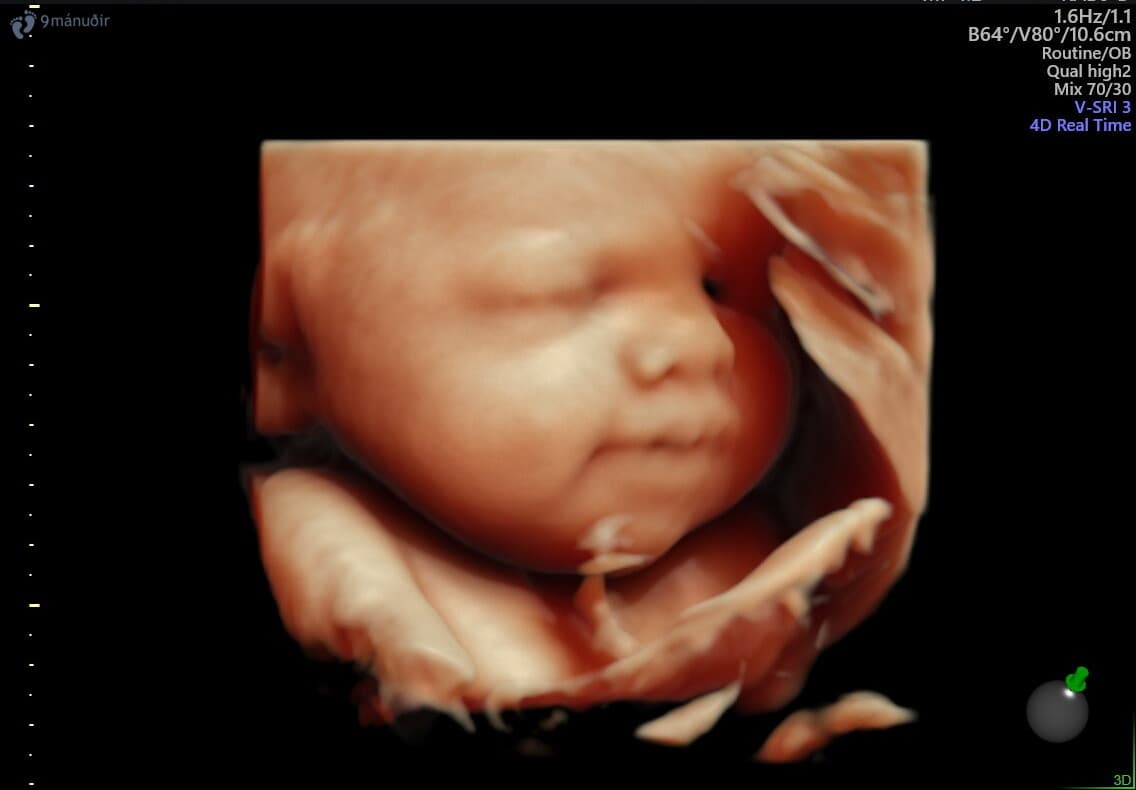

Við bjóðum uppá sónarskoðanir á meðgöngu, snemmsónar, tvívíddar- og þrívíddarsónar og stuttan 15 mínútna sónar.